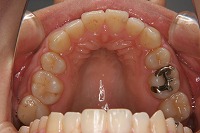

上顎

上の前歯が出ている事を主訴に来院された、23歳2か月の女性です。診断「下顎骨の後方回転による骨格性上顎前突で開咬を伴う」上顎は両側第1小臼歯、下顎は抜歯をせず治療を行いました。